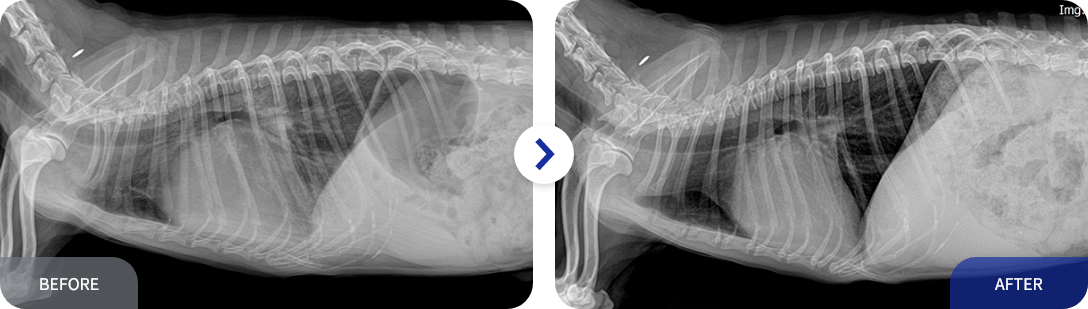

전방십자인대 파열(TPLO)

수술(TPLO)